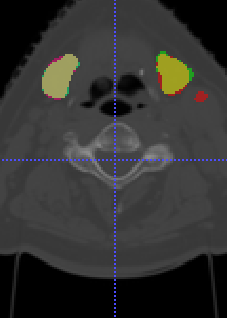

In Chapter 6, we propose an end-to-end, atlas-free 3D convolutional deep learning framework for fast and fully automated whole-volume HaN anatomy segmentation [115]. Our deep learning model, called AnatomyNet, segments OARs from head and neck CT images in an end-to-end fashion, receiving whole-volume HaN CT images as input and generating masks of all OARs of interest in one shot. AnatomyNet is built upon the popular 3D U-net architecture, but extends it in three important ways: 1) a new encoding scheme to allow auto-segmentation on whole-volume CT images instead of local patches or subsets of slices, 2) incorporating 3D squeeze-and-excitation residual blocks in encoding layers for better feature representation, and 3) a new loss function combining Dice scores and focal loss to facilitate the training of the neural model. These features are designed to address two main challenges in deep-learning-based HaN segmentation: a) segmenting small anatomies (i.e., optic chiasm and optic nerves) occupying only a few slices, and b) training with inconsistent data annotations with missing ground truth for some anatomical structures. We collect 261 HaN CT images to train AnatomyNet, and use MICCAI Head and Neck Auto Segmentation Challenge 2015 as a benchmark dataset to evaluate the performance of AnatomyNet. The objective is to segment nine anatomies: brain stem, chiasm, mandible, optic nerve left, optic nerve right, parotid gland left, parotid gland right, submandibular gland left, and submandibular gland right. Compared to previous state-of-the-art results from the MICCAI 2015 competition, AnatomyNet increases Dice similarity coefficient by 3.3% on average. AnatomyNet takes about 0.12 seconds to fully segment a head and neck CT image of dimension , significantly faster than previous methods. In addition, the model is able to process whole-volume CT images and delineate all OARs in one pass, requiring little pre- or post-processing. We demonstrate that our proposed model can improve segmentation accuracy and simplify the auto-segmentation pipeline. These contributions are released as an open-source software package called AnatomyNet, which is publicly available555https://github.com/wentaozhu/AnatomyNet-for-anatomical-segmentation. Portions of this chapter were published as part of [115].